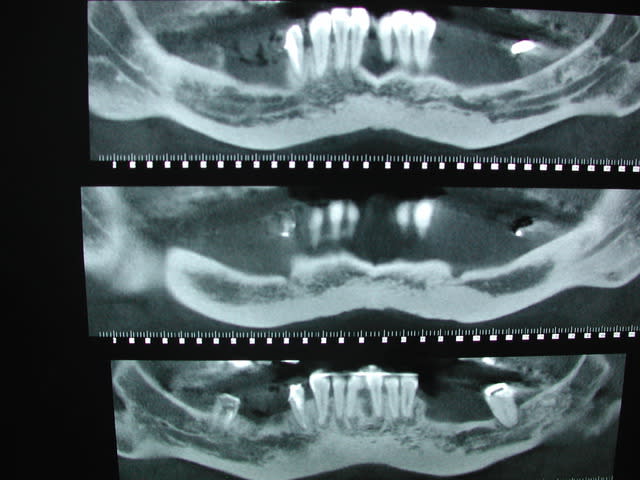

Je reçois hier cette patiente avec ce scan sous le bras

Tes coupes sont très floues...

Sur le pano (2e) les dent sont pas très top...

comme d'ab, +1 avec Céramik, c'est flou, quid du maxillaire, photos.

visiblement os D1, donc bone splitting avec précautions, peut etre implanto en deux temps (os puis implants)